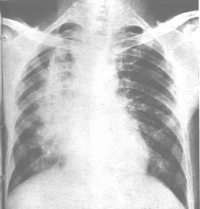

肺功能改变:肺放射性肺炎和纤维化都引起限制性通气功能障碍,肺顺应性减低,伴通气/血流比例降低和弥散功能减低,导致缺氧。有时胸片尚未发现异常,而肺功能检查已显示变化。 X线表现:多数于停止放疗一月后,肺部出阴影。急性期在照射的肺野上出现弥温性片状模糊阴影,其间隐约可见网状影,酷似支气管肺炎或肺水肿。病变的范围与胸廓表面照射野一致。慢性发生肺纤维化,呈条索状或团块状收缩或局限性肺不张。纵隔胸膜和心包有大量粘连,纵隔向患侧移位,同侧横膈升高和胸廓塌陷。

“放射性肺炎”的诊断一般并不复杂,可根据如下依据进行诊断:有放射性治疗史;病人有干性呛咳、进行性气急及肺部的Velcro罗音具有特征性;胸部X线检查可见肺部炎症或纤维化表现。多于停止放射治疗一个月后出现。急性期表现为在照射肺野出现片状或溶合成大片、致密的模糊阴影,其间隐约可见网状阴影,与支气管肺炎或肺水肿极为相似。慢性期表现为肺纤维化,呈网状,条索状或团块状收缩阴影,主要分布于肺门或纵隔两侧及其他放射肺野。由于肺纤维收缩,气管、心脏向患侧移位,同侧横膈抬高,正常肺组织产生代偿性肺气肿。发生肺动脉高压时,表现为肺动脉段突出或右心肥大。常有胸腔积液特征。特别注意的是需与肺转移性癌相鉴别,如果将放射性肺部损伤误作为肺转移性肿瘤,继续放疗,可造成死亡。放射性肺损伤的部位一般与照射野相符,经过一段时间观察肺纤维化后病灶会回缩,而转移癌会继续增大。为了预防放射性肺损伤的发生,应严格掌握放射野、时间和剂量,以尽量避免肺部的损伤。